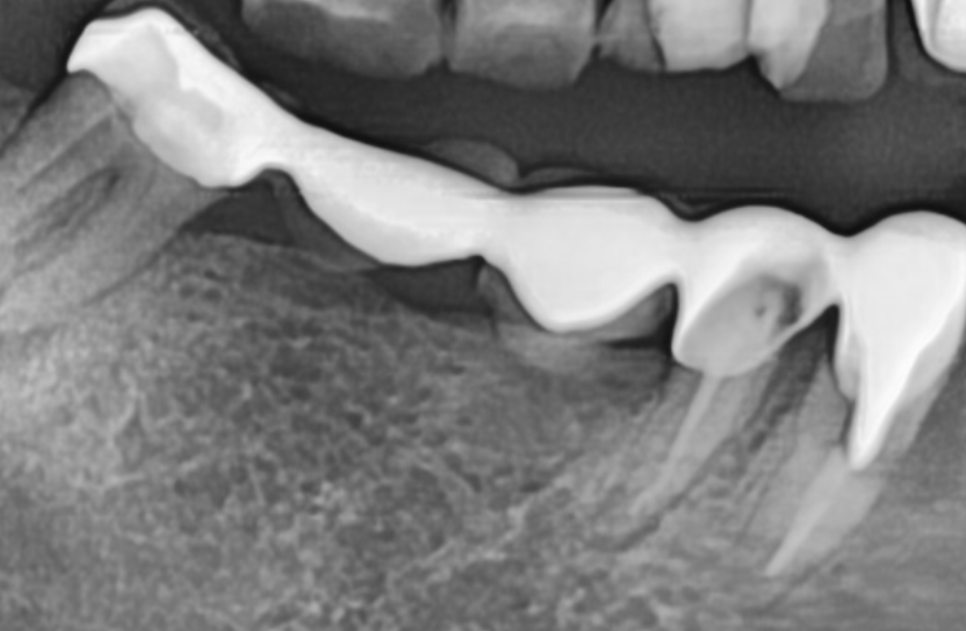

이 환자분은 오른쪽 아래,

무려 5개의 치아를 연결한

긴 브릿지가 통째로 빠져서 오셨는데요.

250507

무엇보다 브릿지를 지탱하던

앞 치아(#43)는

과도한 힘을 버티지 못하고

치아 반쪽이 깨져 있었습니다.